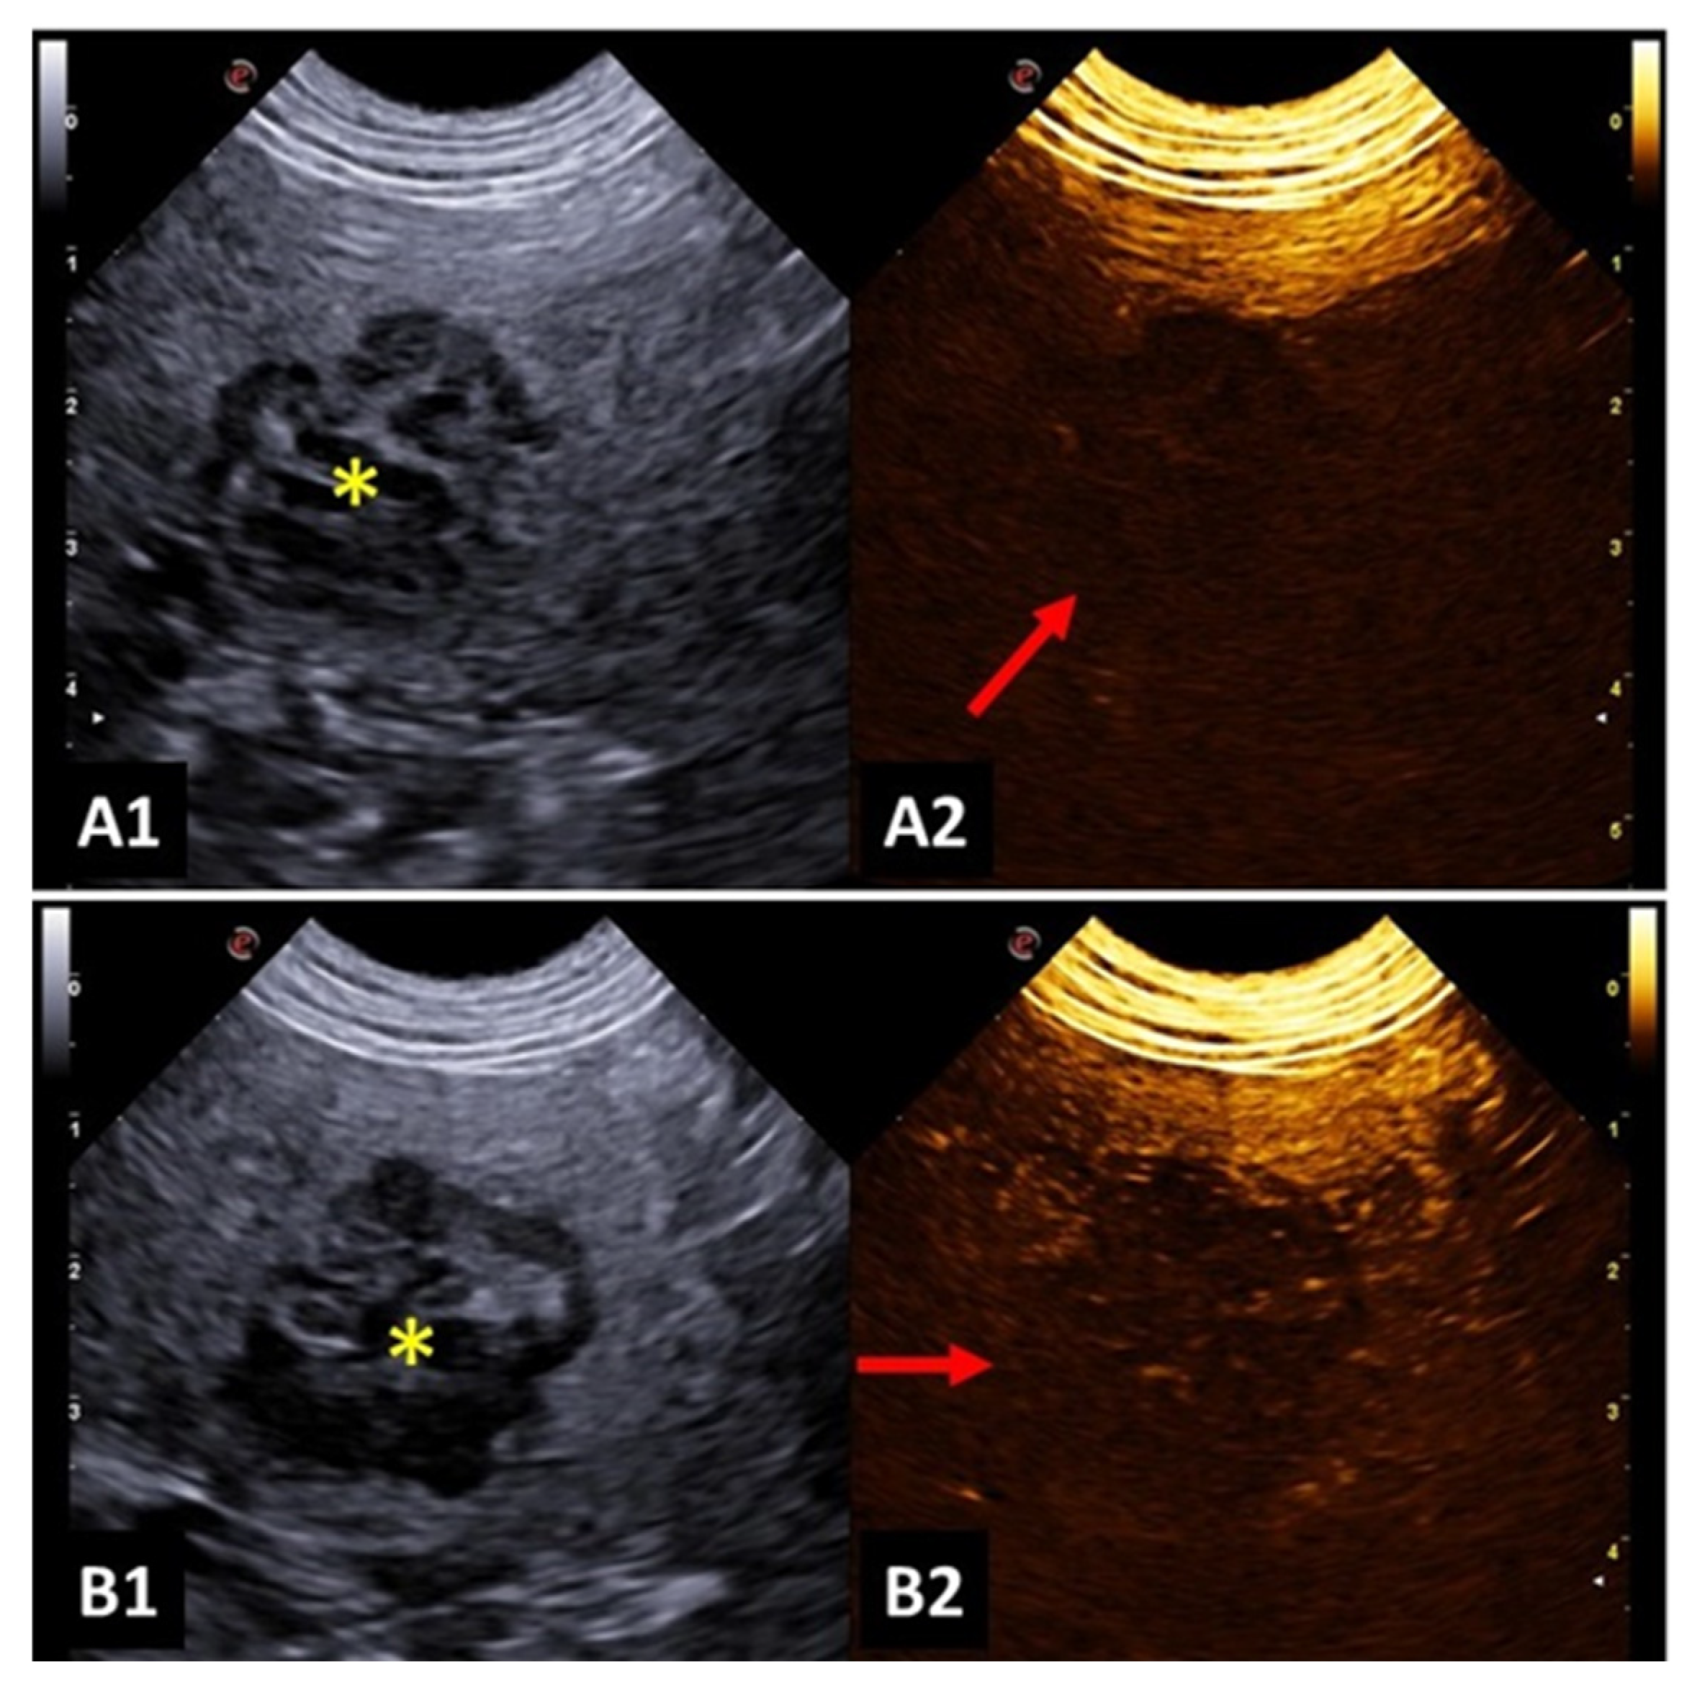

A study investigated focal splenic lesions with CEUS and reported that a hypoechoic lesion during wash-out, associated with tortuous vessels, was suggestive of malignancy (Figure 3). Meanwhile, benign lesions presented a perfusion pattern like the adjacent splenic parenchyma. The same study described that hemangiosarcoma was presented as a large mass, with no perfusion in any phase, surrounded by a hypervascular splenic parenchyma. Lymphosarcoma presented faster time to peak and early wash-out, with a honeycomb enhancement pattern during wash-out [48].

Comparatively, other authors attested that the differentiation of benign and malignant splenic lesions must be based on the vascular tortuosity instead of considering the echogenicity or persistent hypoperfusion. Besides that, fact, hypoperfusion persistent during all contrast phases can suggest malignancy with 40% sensitivity, 80% specificity and 71% accuracy [49].

Figure 3. Image of malignant splenic lesion in a dog: (A1 and B1) B-mode image of the splenic lesion with mixed and heterogeneous echogenicity; (A2) CEUS image before contrast filling; (B2) hypointense splenic lesion during contrast wash-out, indicating characteristics of malignancy.